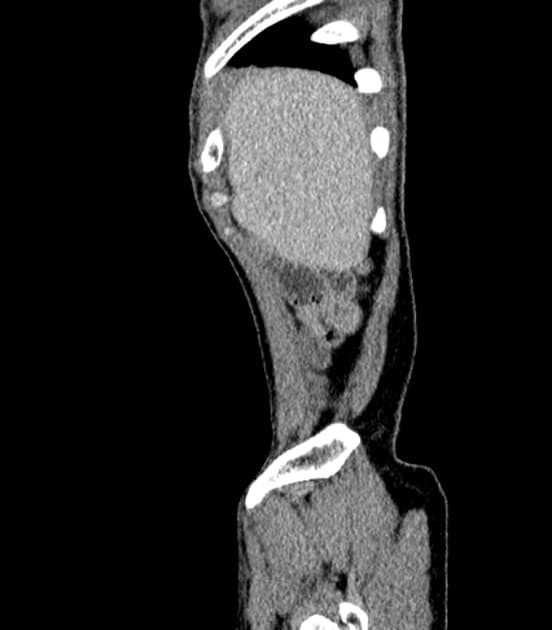

Sagittal non-contrast

Ca bệnhGãy xương đốt sống bệnh lý

Gãy xương đốt sống bệnh lý

- Có tổn thương di căn phá hủy tại đốt sống L1, xâm lấn gần như toàn bộ thân đốt sống và lan vào cuống cung (pedicle), bên phải nặng hơn bên trái, lan vào mấu ngang phải, đồng thời phá hủy vỏ xương và bản tiếp hợp (end-plates).

- Có gãy nén thân đốt sống (vertebral compression fracture) với mức độ mất chiều cao tối đa là 55%.

- Tổn thương lan vào ống sống trung tâm (central canal) gây hẹp ống sống (canal stenosis).

- Có xâm lấn mô mềm ngoài xương (extraosseous) vào mô quanh đốt sống bên phải và vào các lỗ liên hợp (neural foramina) T12/L1 và L1/L2 hai bên, mức độ hẹp tối đa tại L1-L2 bên phải.

Gãy xương đốt sống bệnh lý (pathological vertebral fracture)